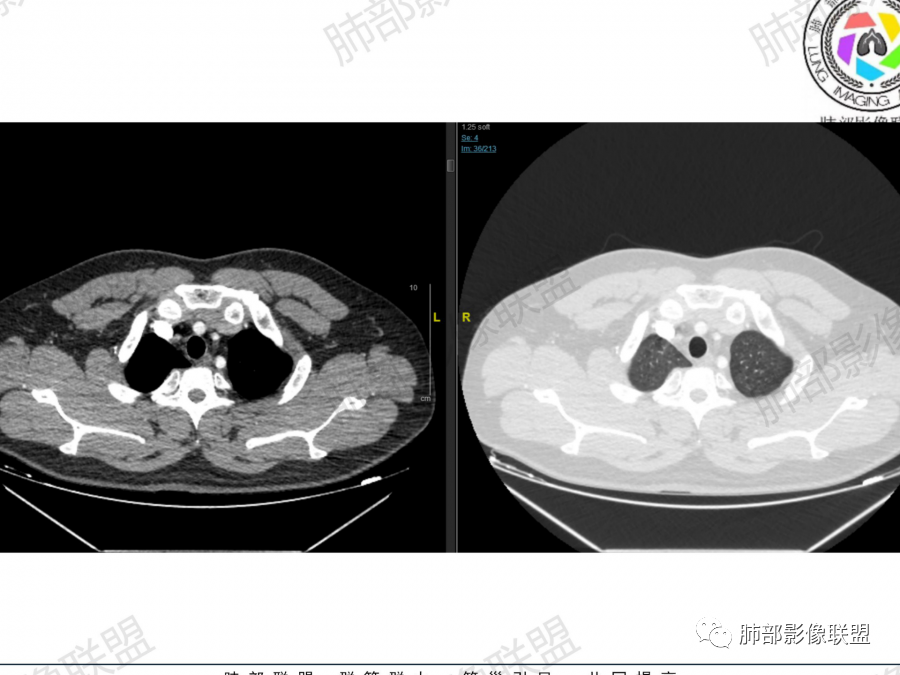

中年男性,咳嗽气喘一个月,血象不高,双肺野多发肿块,右肺上叶,右肺下叶胸膜下,近脊柱旁,肿块有膨隆有收缩,似多结节融合,内有多发小空泡,边缘似有晕,支气管进入走形比较自然,血管进入,走形自然,支气管阻塞不明显,考虑感染性病变,隐球菌可能,鉴别血管炎。

青中年男性患者,咳嗽、气喘1月,铁蛋白增高,抗组蛋白抗体及D二聚体增高,胸部CT:右肺上叶尖段大片实变影,似乎有结节融合而成,边界清楚,内部见扩张的支气管及血管影,增强扫描轻度不均匀强化,右肺下叶见多发类似病灶,有沿支气管分布趋势,综合考虑感染性或炎性病变,首选结核,次选血管炎,鉴别淋巴瘤

典型,青年男性,有铁蛋白增高,有免疫异常,胸膜下,长轴平行胸膜,病灶内血管走行自然。

青年人,没有纵隔淋巴结肿大,没有肝脾肿大,没有发热,尽量不要轻易考虑淋巴瘤

1、青年男性、咳嗽气喘一月,加重两天入院。实验室检查:有铁蛋白增高,血脂、肝功异常、有免疫异常。

2、右肺多发结节影,大者位于右肺上叶尖段,内可见空洞,空洞内壁欠规整,内可见分隔,余结节位于胸膜下、结节大小不等、形态相近,强化均匀,内部可见血管穿行,血管及支气管走行自然。结合临床及影像,符合隐球病。